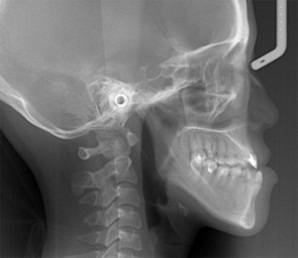

放射检查:一般包括X线头影测量片、曲面体层片和CBCT(锥束CT)。有时还包括其他放射检查,比如螺旋CT等。通过放射检查,医生能够看到骨骼及牙齿的形态、位置及发育状况,以及是否有牙体、根尖周、牙周疾病等,从而评估是否需要正畸治疗、进行何种治疗。

(摘自“第三章第一节正畸的基本知识”)

头影测量片(上)、曲面体层片(中)和锥束CT(下)